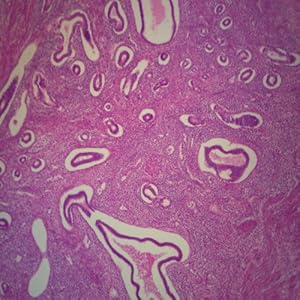

Human Prostate Gland – Young, sec. 7 um, H&E